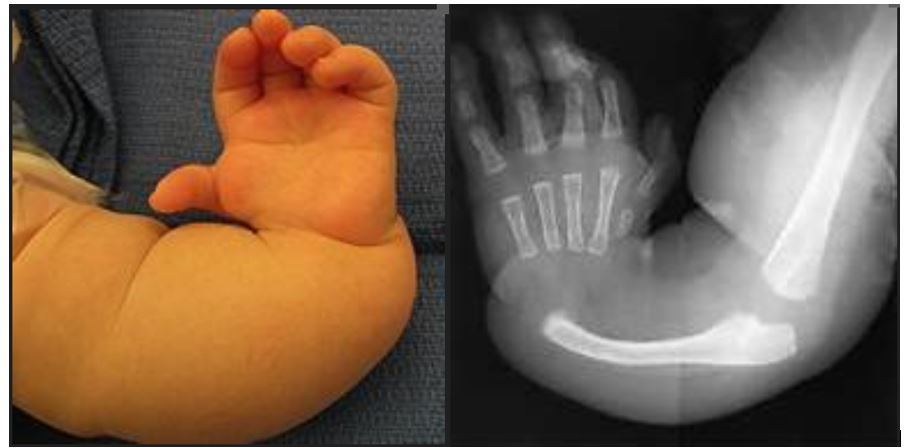

7-month-old boy has this upper limb deformity. The initial work-up is negative for any cardiac, hematopoetic or renal abnormalities. He has good active elbow flexion and no other deformities.

1. What is your diagnosis?

2. What classification is used? How will you classify this child’s limb?

3. What is the best management for this patient? Why?

A

1. Non-syndromic radial longitunidal deficiency (RLD)/ radial club hand.

2. This child is Type 4

Bayne and Klug- 4 types

Type 1- short distal radius

Type 2 – short distal radius with residual growth plates

Type 3 – small proximal radius

Type 4 – absent radius

3.Ulna centralization and possible tendon transfers

He has a viable thumb with good active elbow flexion (elbow joint not stiff, good bicep function),

Therefore the treatment of choice is centralization and tendon transfers to re-establish balance across the wrist.

The goal of centralizing the carpus on the ulna is to improve reach and to stabilize tendons and muscle balance across the wrist.

Q

1. Describe this clinical finding.

2. Name the common classification used.

3. What are management considerations & options for this patient.

4. What age will you propose these management options

1.Deformity of the hand- absent thumb.

Hand is perpendicular to the forearm.

Radial clubhand (Radial longitudinal deficiency)

1. Bayne and Klug- 4 types

Have to use plain radiograph to determine which type patient is in.

3.

Considerations:

• age

• elbow flexion ability (bicep deficiency, supple elbow joint/synostosis of ulnohumeral joint)

• absent/presence of thumb

a) Conservative by passive stretching and observation.

Indication: Absent elbow motion, biceps deficiency.

b) Operative

i) Hand centralization

Aim: to centralize the carpus on the ulna to improve reach and to stabilize tendons and muscle balance across the wrist.

Indication: Good elbow motion and biceps function intact.

Method: Resection of varying amount of carpus, shortening of ECU, angular osteotomy of ulna, distraction external fixator

ii) Tendon transfer

iii) Thumb reconstruction/ pollicization if absent

4. Age 6-12 months

Not too young, when it is not safe for child to undergo anaesthesia